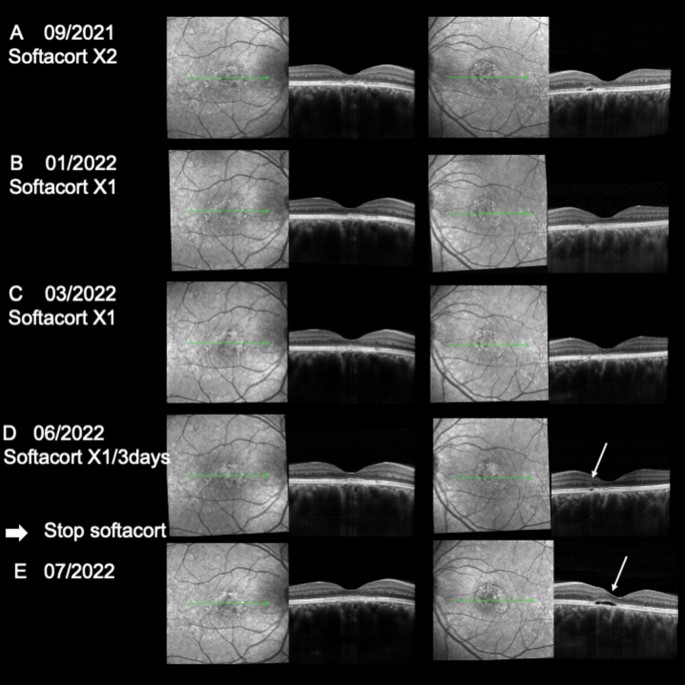

At presentation, best corrected visual acuity was 8/10 on both eyes and the patient complained of micropsia and loss of contrast. On spectral domain optical coherence tomography (SD-OCT) B scan, subfoveal choroidal thickness was 680 µm in the RE and 516 µm in the LE with massive dilation of choroidal veins and effacement of the choriocapillaris. Macular subretinal fluid was present in both eyes (Fig. 8D). FA and ICG angiography performed in January 2021 showed a faint leaky site nasal to the fovea in the right eye and no leaky site on the left eye with mid-phase hyperfluorescent plaques more pronounced in the left than in the right eye along temporal vessels, at 7 min (Fig. 8A,B). No sign of choroidal neovascularization was found on ICG-A or on optical coherence tomography angiography (OCTA). Eplerenone 50 mg was introduced in January 2021 resulting in reduction of SRF at 1 and 3 months but without complete resolution of the SRF (Figs. 8E,F). Preservative free dexamethasone drops (twice per day) were introduced in July 2021 resulting in almost complete resolution of SRF at 15 days in both eyes (Fig. 8G). The patient was followed with complete resolution of SRF in both eyes and she was maintained on dexamethasone 1 drop/day without any raise in intraocular pressure for 2 months (Fig. 9A). The vision was 10/10 when she was switched to Softacort® 1 drop/day and remained free from recurrence until June 2022 (Fig. 9B,C), where an initial minimal increase in SRF appeared on OCT upon reduction of drop to 1 every 3 days (Fig. 9D). Recurrence of SRF was observed in the left eye 3 weeks after she had stopped all treatments (Fig. 9E).

SD-OCT follow-up after glucocorticoid switch. (A–C) After hydrocortisone switch and slow tapering, a complete absence of CRF was documented, together with a good photoreceptor (PR) layer reconstitution and mild RPE irregularities. (D) Upon furtherly tapering hydrocortisone to 1 drop every 3 days, a minimal PR detachment was observed (white arrow) in the left eye. Glucocorticoid treatment cessation and close follow-up at 3 weeks (E) revealed an initial recurrence of the disease in the left eye corresponding to the same perifoveal area (white arrow).